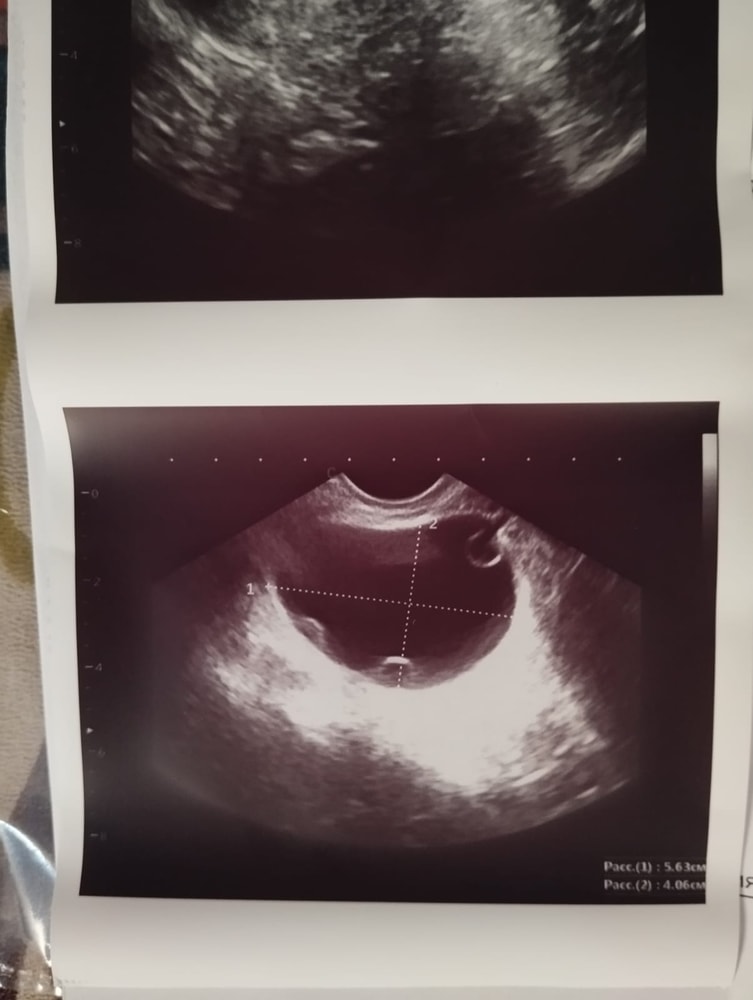

Была задержка месячных на 10 дней, затем начались мазня, пошла на изи, сказали киста на яичники 5.6 мм, пила Транексам, кровь не остановилась, пошла к другому врачу, киста подтвердилась, сказала ничего не пить сама пройдёт, уже прошло достаточно времени пошла к 3му врачу, сказали сидеть анализы на онкомаркеры и сказали что если кровь не пройдёт, придётся делать вакуум.Подскажите пожалуйста, что делать и как остановить кровотечение?